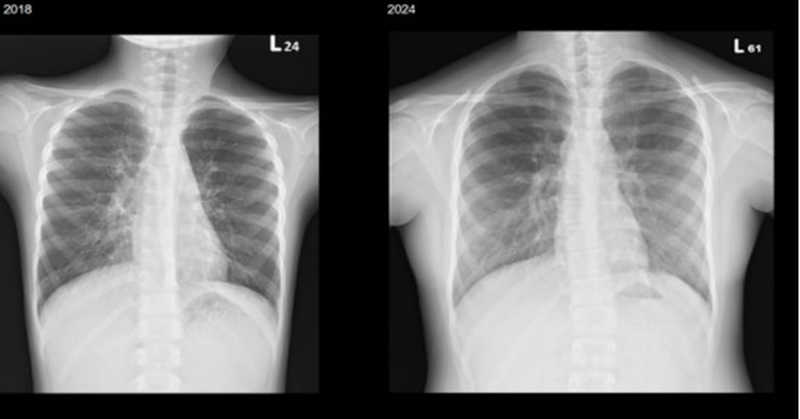

▲林小妹於2018年、2025年所攝胸部X光片,楊佳鳳主任表示,成像愈黑,代表肺功能較好,可見她歷經7年專業照護,肺功能維持穩定。(圖/北榮提供)